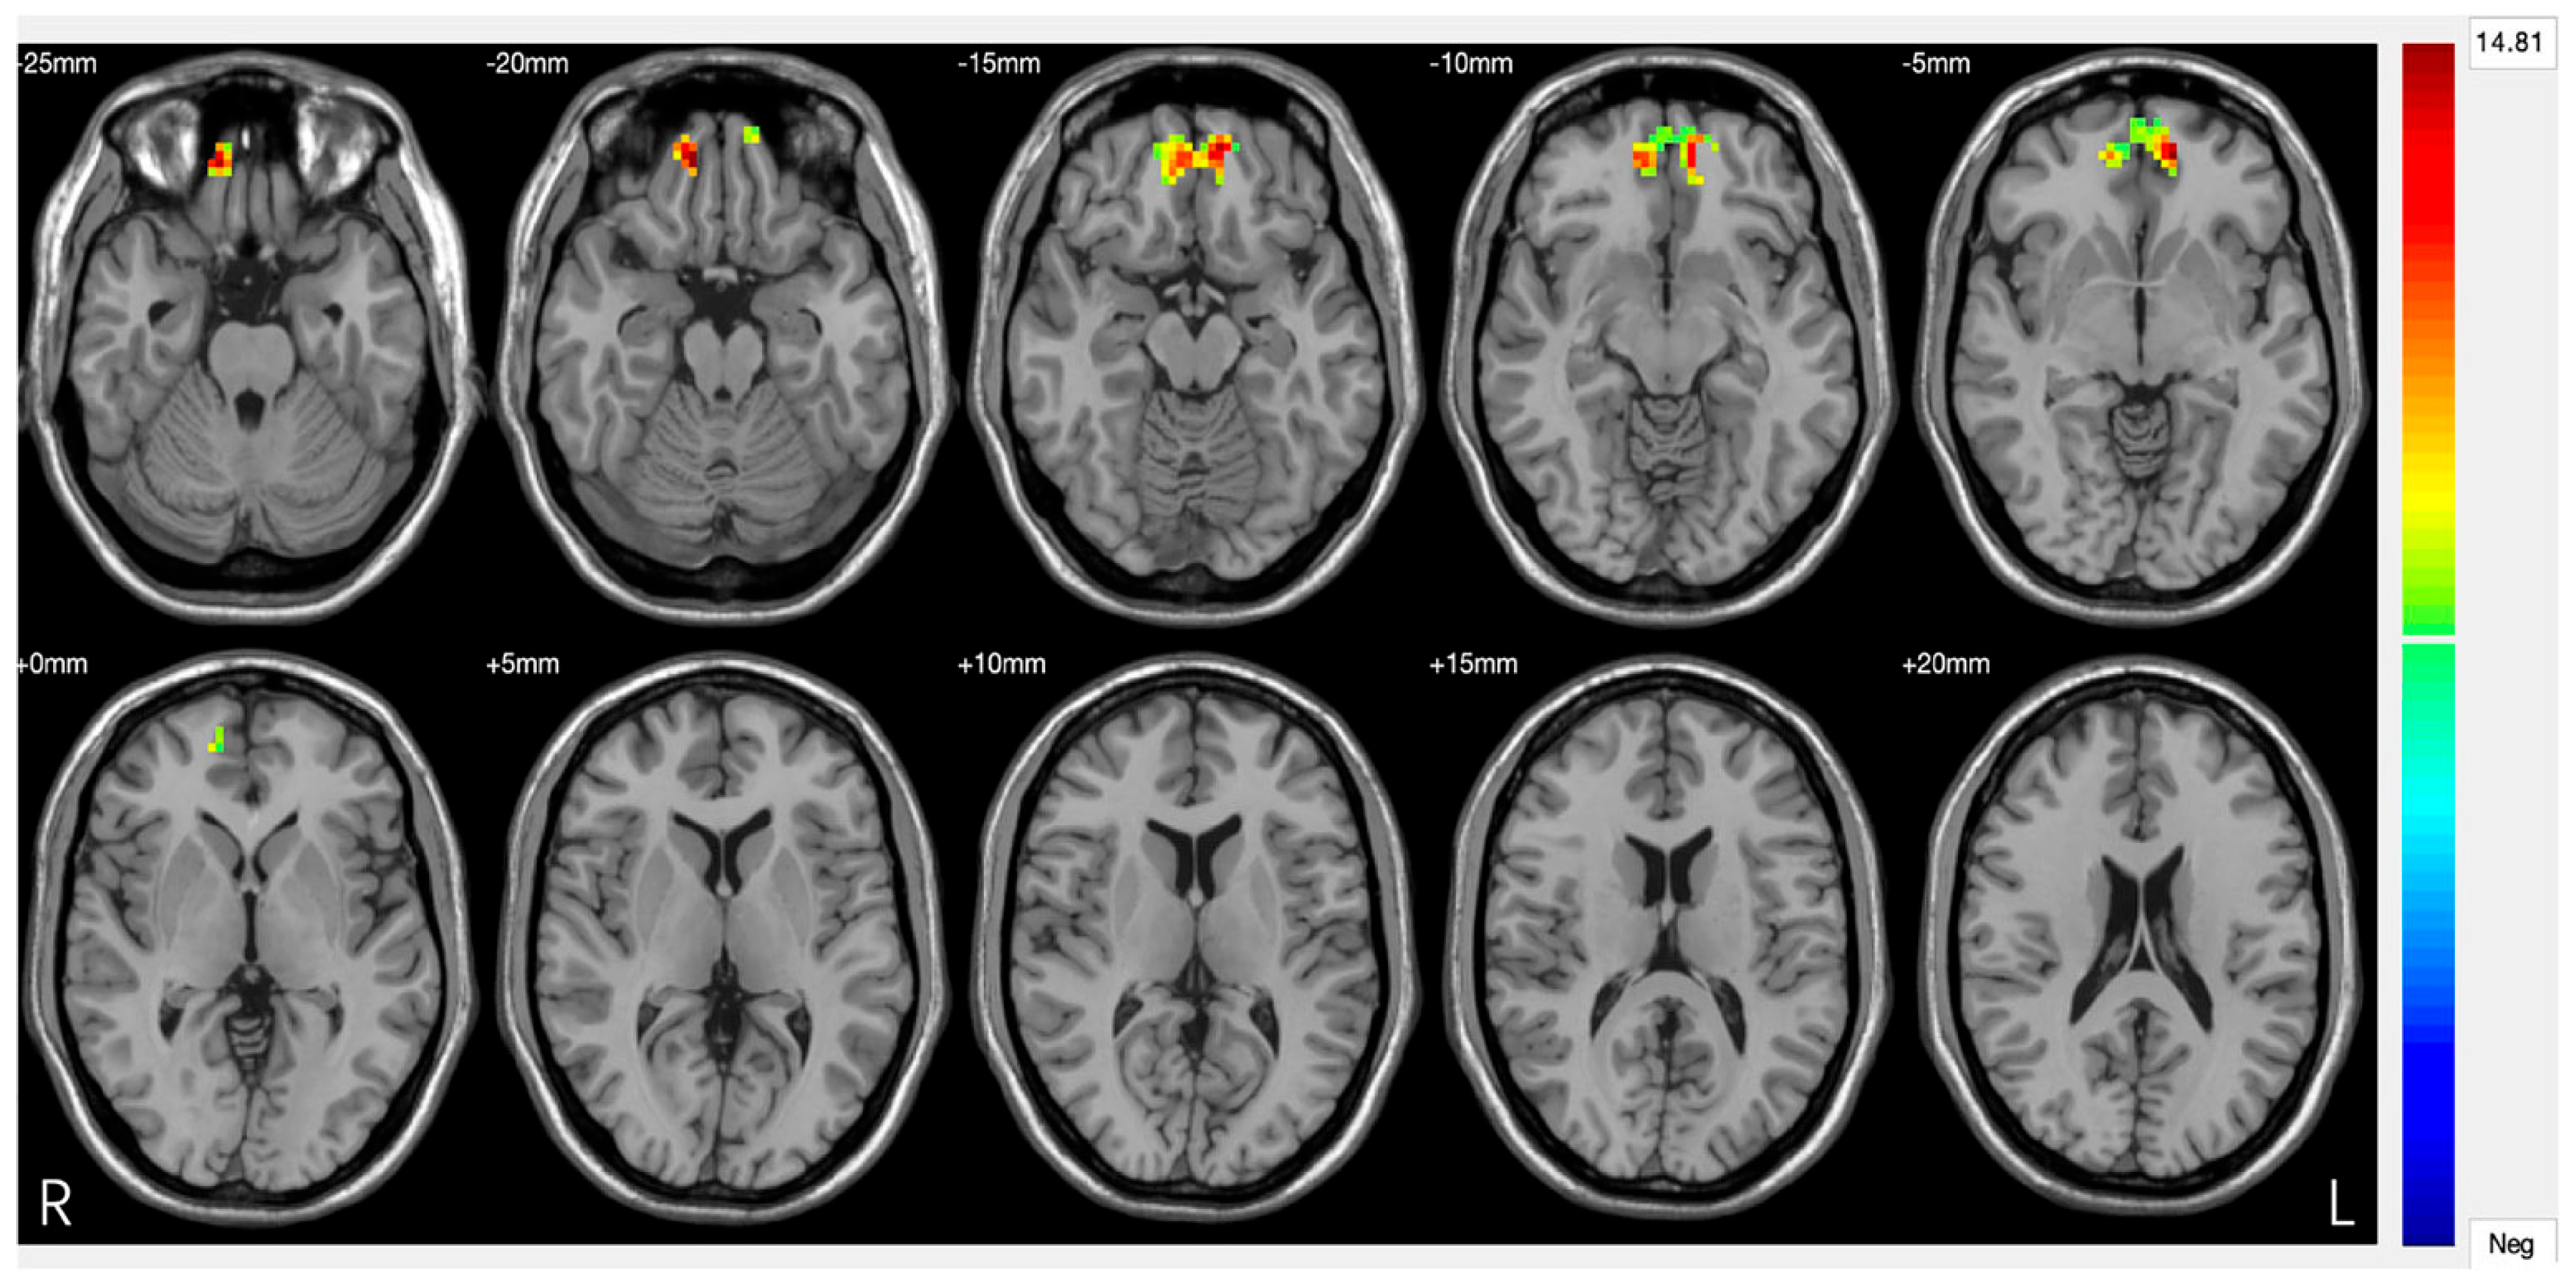

Amygdala. The amygdala serves as a crucial neural hub in depressive pathophysiology, representing the primary centre for negative emotion processing and threat response coordination [62]. Functional alterations of this structure result in pathological amplification of negative emotional responses while compromising fear extinction mechanisms, significantly contributing to the emotional dysregulation characteristic of DS. Neuroimaging studies consistently document amygdala hyperactivation patterns in response to negative emotional stimuli, with BOLD activity increases of 40–60% compared to healthy controls [63]. This hyperresponsivity shows selective characteristics, being particularly pronounced for negatively valenced stimuli while paradoxically reduced for positive stimuli, suggesting specific dysregulation of emotional processing circuits rather than generalized emotional reactivity (Figure 3). The basolateral amygdala demonstrates specific alterations in synaptic plasticity, with reduced GABAergic inhibition effectiveness leading to increased neuronal excitability [64]. High-resolution magnetic resonance studies have revealed microstructural modifications, including 12–18% increases in cellular density that correlate with symptom severity [65]. Connectivity between the amygdala and VMPFC shows significant compromise in DS, with 30–45% reductions in functional synchronization during emotional regulation tasks [66]. This disconnection compromises prefrontal top-down modulation effectiveness, perpetuating amygdala hyperactivation and limiting cognitive emotional control capacity. Diffusion tensor imaging studies have identified corresponding white matter alterations in tracts connecting the amygdala to the orbitofrontal cortex, with 15–25% reductions in fractional anisotropy correlating with depressive symptom intensity [67].

Figure 3.

Significant differences in amygdala–prefrontal cortex (PFC) functional connectivity (FC) among the major depressive disorder (DS) with a history of suicide attempts (SA), DS without a history of SA, and HC groups. Significant at p < 0.001, corrected by Gaussian random field (GRF) correction [68].